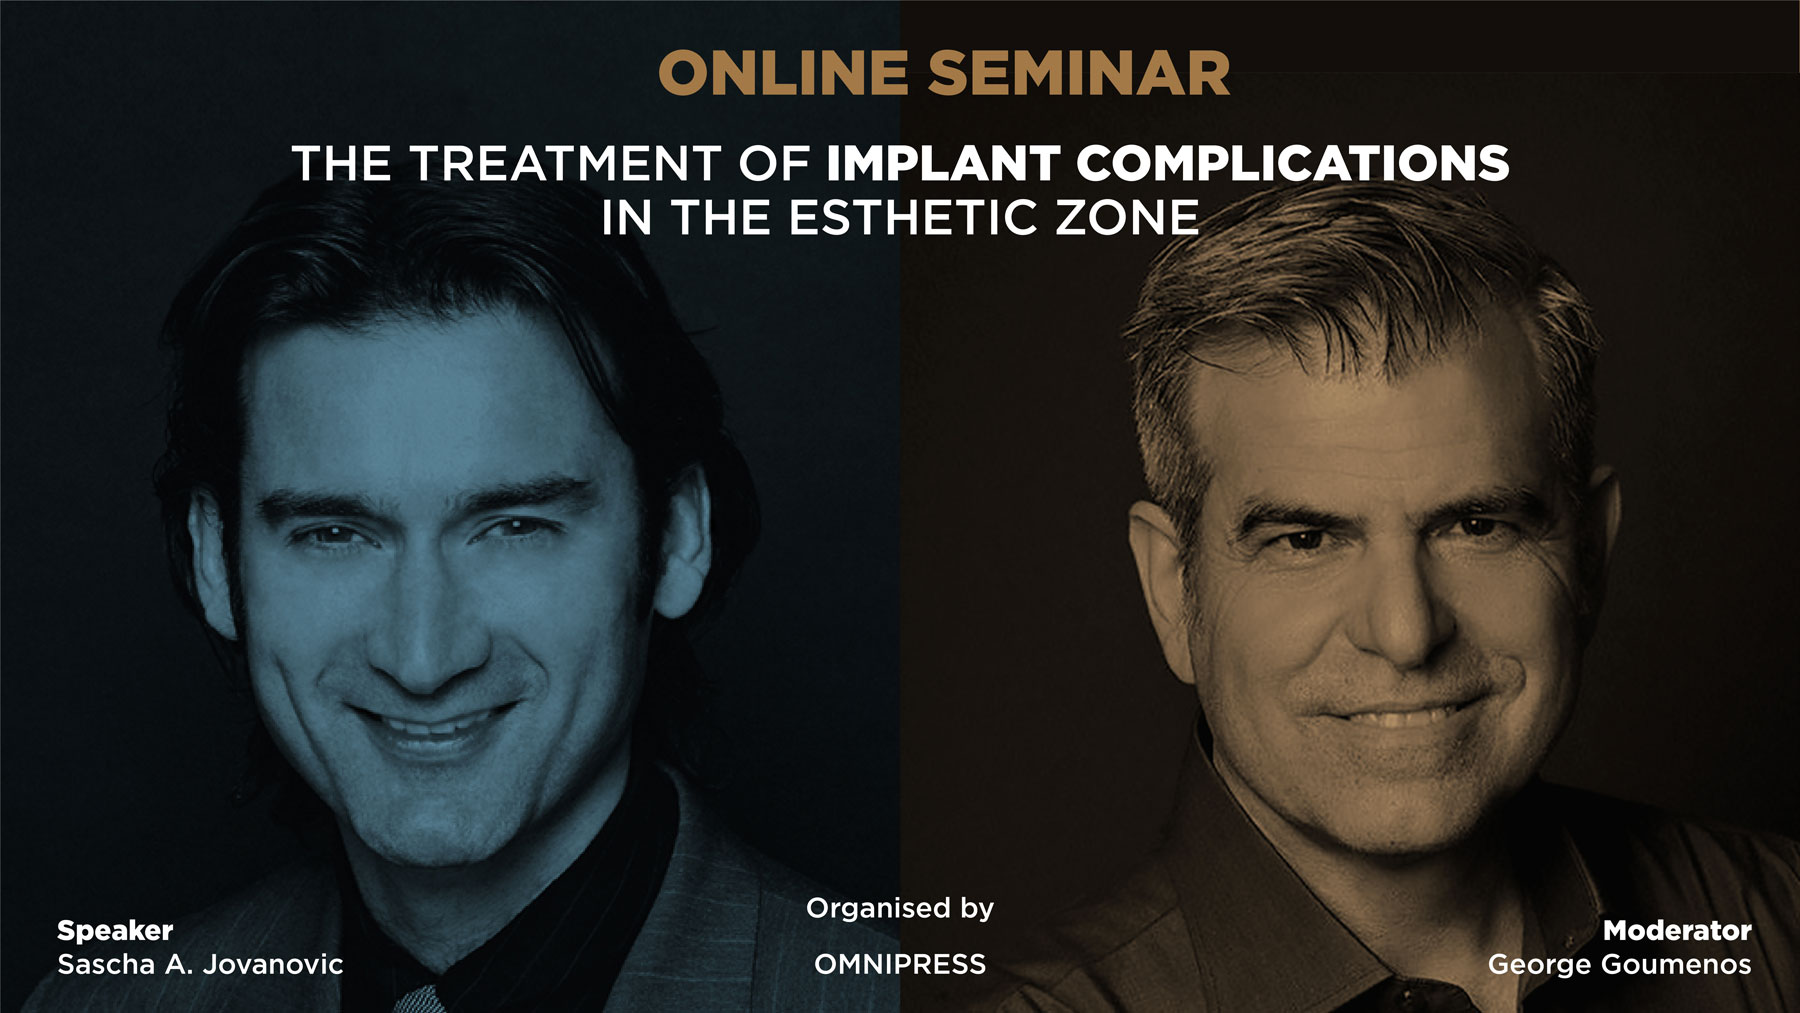

Dental Implants and osseointegration have established themselves as a major scientific breakthrough which revolutionized clinical dentistry. Complications occur but are minimal when proper patient selection, evidence based biomaterials and clinical protocols are followed. The treatment with a higher complication rate is the esthetic zone. This is unfortunately true as the patient expectation are high for optimal and natural esthetics, the anatomy of the anterior jaw bone is often thin and resorbed and the clinical skills and knowledge to manage these complex anterior esthetic cases are often not available.

This online lecture will present in detail the clinical challenges of treating the anterior zone and the most frequently seen complications. Scientific evidence and clinical protocols will be given to present the steps to diagnose, prepare, plan, treat and follow the patient in these esthetic complex situations.

Surgical protocols in GBR planing and grafting, soft tissue augmentation and the optimal implant placement will be presented in lecture formal and in the form of a live surgery documentation.

Speakers

George Goumenos

GREECE

Dr. Goumenos graduated from the School of Pharmacy (University of Athens, Greece) in 1982 and the School of Dentistry in 1988. He graduated from the Dpt. of Periodontology of Tufts University, School of Dental Medicine, Boston, where he obtained his Certificate in Periodontology in 1990 and his Master of Science Degree in 1991 from the Graduate School of the same University. He received a Doctorate Degree in 1998 from the Dpt. of Periodontology, of the University of Athens, Greece.

Dr. Goumenos was announced Diplomate of the American Board of Periodontology in 1996.

He was appointed Adjunct Clinical Assistant Professor at the Dpt. of Periodontology, Tufts University, Boston, and since 1991 he has been a clinical instructor at the Dpt. of Periodontology of the University of Athens, Greece.

He has published several articles to date and he is lecturing both nationwide and internationally; he is a faculty member of gIDE and a member of AAP, EFP, AAO and EAO.

His main interest is in the biology of oral tissues and their management in periodontal and implant reconstructive plastic surgery.

Dr. George Goumenos has been in private practice since 1992, devoted exclusively to Periodontics and Dental implants in Athens, Greece.

Sascha Jovanovic

U.S.A.

Sascha A. Jovanovic was formally trained in periodontics at UCLA School of Den-tistry, in Implant Dentistry at Loma Linda University and in Prosthodontics at Univer-sity of Aachen, Germany and holds a Master of Sciences degree in Oral Biology from UCLA.

He restricts his clinical work to dental implant therapy and bone & soft tissue reconstruction, is Course Director at UCLA Continuing Education, is Professor (Hon.) at Univ. of British Columbia, Division of Periodontics and Implants, Vancouver, is Assoc. Prof. (Hon.) at the University of Hong Kong, Department of Oral Surgery and is Founder and Academic Chairman of the gIDE Institute.

He is the past-president of the European Association for Osseointegration (EAO) and a past-Board member of the Osseointegration Foundation (OF). He was the program chair of the EAO 2000 annual scientific congress, recipient of the young investigator fellowship of the American Academy of Periodontology, of the Implantology award of the California Society of Periodontists and of the German Implant Society Research award. He is an honorary member of the South African Society of Periodontology.

Dr. Jovanovic's clinical research emphazises esthetic management in dental implant therapy and bone and soft tissue reconstruction techniques. His applied research focu-ses on bone regeneration with different bone graft materials, rhBMP-2 and barrier membranes as well as the biology of soft tissues around teeth and implants.

He lectures extensively worldwide and has published over 60 articles and book chap-ters, and one textbook titled Color Atlas of Implantology (Thieme Publ.). He is the Editor-in-Chief of the monthly publication 'Implant Tribune', is on several editorial boards for scientific journals and has published a DVD-education series 'Advanced Implant Therapy'.